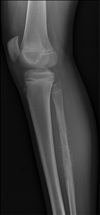

48

What are the preferential locations of primary osteosarcomas?

- metaphysis - tubular long bones (LE; only 3.5-7% in spine) - femur - tibia - humerus - pelvis - spine

49

What radiographic appearance is associated with a primary osteosarcoma?

cumulus cloud appearance (blastic lesion)

50

What are the radiographic findings specific to an osteoblastic osteosarcoma?

- cumulus cloud appearance - lobulated ossified soft tissue mass

What are the radiographic findings of a primary osteosarcoma?

- osteoblastic or permeative osteolytic - cortical destruction - aggressive periosteal Rxn - soft tissue mass not always ossified

10 year old boy with lower leg pain and swelling. What is on your list of differential diagnoses in order from most to least likely?

Aggressive in kid = OLEO 1. Osteomyelitis 2. Osteosarcoma (metaphyseal) 3. Ewing sarcoma 4. Lymphoma

82

18 year old with pain and swelling of the lower leg. What is on your list of differential diagnoses in order from most to least likely?

Aggressive in kid = OLEO 1. Osteosarcoma (metaphyseal) 2. Ewing sarcoma 3. Lymphoma 4. Osteomyelitis (blastic = infection 4th)